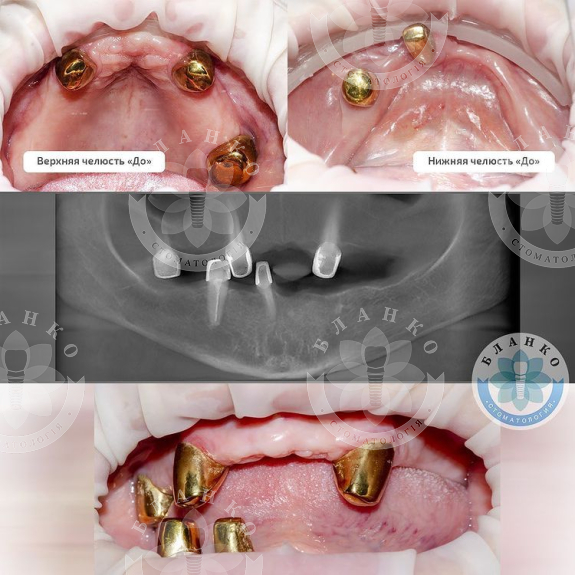

В данной ситуации в первое посещение были удалены оставшиеся зубы, пораженные пародонтитом ( 5 штук ).

Сразу установлено 10 имплантов.

Сделаны временные протезы на имплантах.

Через 4 месяца постоянное протезирование двумя несъёмными конструкциями на верхней и нижней челюсти.